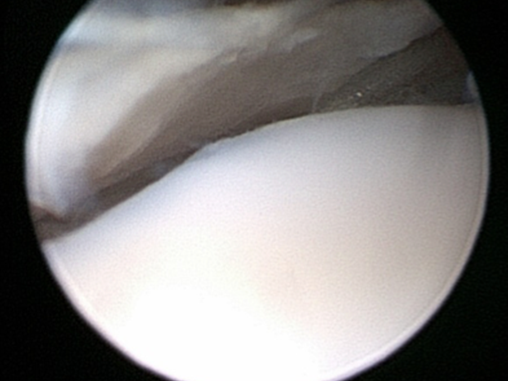

- Osteocondritis Dissecans (OCD). This is a condition in young large breed dogs and results in a flap of cartilage and bone coming free from the back of the humerus. Removal of this flap by arthroscopy or arthrotomy will help settle the problem but there will always be a defect in the joint surface. In most cases this is not a clinical problem but in some where the defect is very large it can be a problem. In cases that have large lesions seen on CT we may suggest resurfacing with a synthetic plug inserted in to the OCD lesion. This is called a SynACART and does require a fairly large exposure and open surgery.